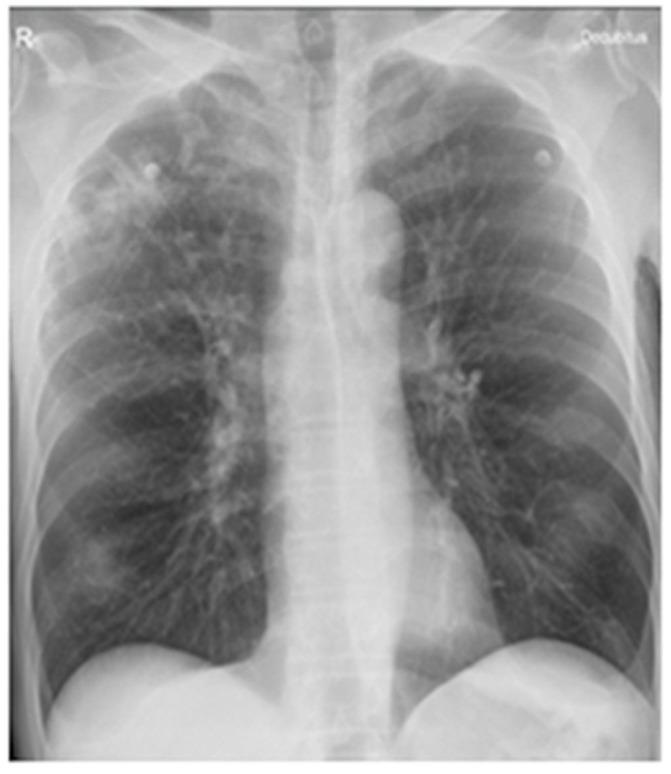

Tuberculosis and parasitic infections, including , frequently coexist in many regions worldwide, yet their interaction remains poorly understood. Tuberculosis triggers a type 1 immune response characterized by IL-12, IFN-γ, and TNF-α production, while toxocariasis elicits a type 2 response, mediated by cytokines such as IL-4, IL-5, IL-13, and IL-33. The coexistence of these divergent immune pathways can disrupt immune regulation and impair the host's ability to control both infections, potentially leading to persistent hypereosinophilia. We illustrate this complex interplay through a real-world case involving a heavy smoker in whom infection likely reactivated latent tuberculosis, resulting in severe, unexplained hypereosinophilia and late-onset asthma with recurrent exacerbations. After excluding other causes and completing full antituberculosis therapy along with three courses of antiparasitic treatment and systemic corticosteroids, hypereosinophilia persisted. The introduction of benralizumab, a biologic therapy targeting IL-5Rα, led to a rapid reduction in eosinophils to normal ranges and significant clinical improvement. This case underscores the diagnostic and therapeutic challenges posed by the intersection of common infections and highlights that even a neglected parasitic infection such as toxocariasis can underlie severe respiratory complications with eosinophilia, where paradoxically biologic therapy may ultimately provide a very effective intervention.

结核病和寄生虫感染(包括 )在世界许多地区经常同时存在,但其相互作用仍知之甚少。结核病引发以产生白细胞介素-12、干扰素-γ和肿瘤坏死因子-α为特征的1型免疫反应,而弓蛔虫病引发由白细胞介素-4、白细胞介素-5、白细胞介素-13和白细胞介素-33等细胞因子介导的2型反应。这些不同免疫途径的共存会破坏免疫调节,损害宿主控制两种感染的能力,可能导致持续性嗜酸性粒细胞增多。我们通过一个实际病例来说明这种复杂的相互作用,该病例涉及一名重度吸烟者,其中 感染可能使潜伏性结核病重新激活,导致严重的、原因不明的嗜酸性粒细胞增多以及反复发作的迟发性哮喘。在排除其他原因并完成全程抗结核治疗以及三个疗程的抗寄生虫治疗和全身用糖皮质激素治疗后,嗜酸性粒细胞增多仍然存在。引入靶向白细胞介素-5受体α的生物疗法贝那利珠单抗后,嗜酸性粒细胞迅速减少至正常范围,并取得了显著的临床改善。该病例强调了常见感染交叉所带来的诊断和治疗挑战,并突出表明,即使是像弓蛔虫病这样被忽视的寄生虫感染也可能是嗜酸性粒细胞增多导致严重呼吸道并发症的基础,在这种情况下,生物疗法最终可能提供非常有效的干预措施。